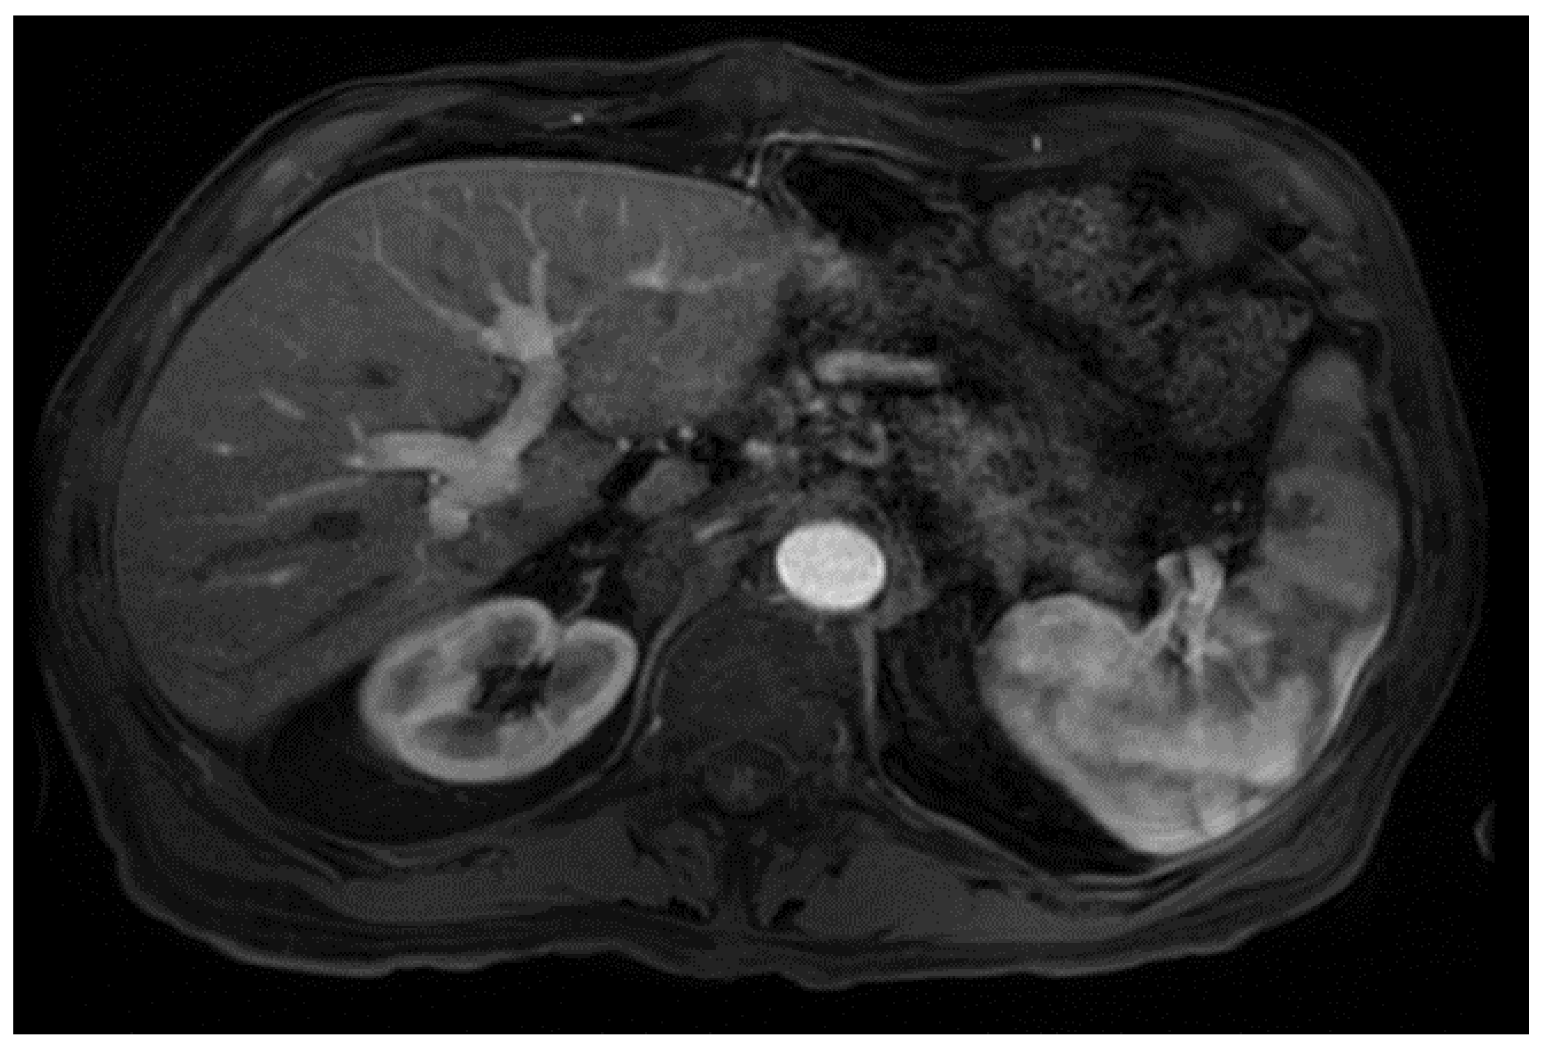

He was admitted for tumor evaluation which revealed a poorly differentiated, multifocal, grade 3 HCC. The Liver Imaging Reporting and Data System (LI-RADS) score was 5 (for arterial enhancement, washout, and size greater than 20 mm). Mild intrahepatic biliary dilatation secondary to mass effect was also noted. The tumor was confined to the liver with clear margins, no vascular invasion, normal regional lymph nodes by imaging criteria, and no evidence of distant metastasis, as can be seen in Figure 1.

Figure 1.

Magnetic resonance imaging of the abdomen. Limited by motion. Cirrhosis and splenomegaly were noted. Infiltrative segment 7 mass measures 6.5 × 4 cm. (A) Diffusion-weighted imaging (DWI) shows diffusion restriction of mass; (B) T1 with contrast shows vague arterial phase enhancement; (C) T1 post-contrast delayed phase imaging shows washout (captured at the diagnosis visit, and before the atezolizumab plus bevacizumab started).